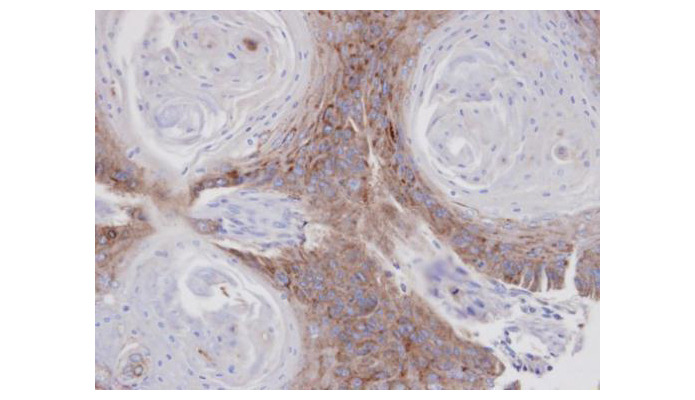

Supportive validation

- Submitted by

- Aviva Systems Biology (provider)

- Main image

- Experimental details

- Immunohistochemical analysis of paraffin-embedded Cal27 xenograft, using ANXA7(OAGA00390) antibody at 1:100 dilution.